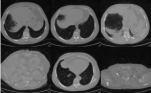

Refer to caption

Figure 3: Comparison of generated results from multiple perspectives for “52 years old male: Fusiform dilatation in the thoracic aorta. Hepatomegaly, hepatosteatosis. Hiatal hernia. Hypodense nodule in the right thyroid lobe.” (a) Comparison of axial slices from GenerateCT, our method, and ground truth (GT), arranged left to right from diaphragm to clavicle, with each method displaying the upper, middle, and lower thorax (frames 9-18, 174-183, and 379-388). (b) 3D rendering comparison highlighting the skeleton, thoracic cavity, and key lung structures. (c) Segmentation results on generated volumes in axial, sagittal, and coronal views, with corresponding 3D renderings.

Spatiotemporal Consistency. Fig. 3 (a) illustrates the temporal coherence of the generated sequences and the adaptability of TRACE in producing volumes of variable lengths. We extracted multiple axial slices from three key anatomical regions, extending from the diaphragm to the clavicle, including the lower thorax (lung base), middle thorax (lung hilum), and upper thorax (lung apex). As seen in the middle row of Fig. 3 (a), TRACE demonstrates smooth transitions across frames, capturing subtle anatomical variations while maintaining spatial consistency throughout the volume. This consistency is evident in the continuity of anatomical structures such as ribs, vertebrae, and lung fields across adjacent slices. In contrast, GenerateCT exhibits noticeable discontinuities and inconsistencies between frames, with abrupt anatomical changes that may impede clinical interpretation. Furthermore, TRACE generates volumes of arbitrary lengths without sacrificing temporal coherence, an essential feature in medical imaging, where scan lengths vary according to diagnostic requirements. The consistent quality across sequences of different lengths highlights the scalability and robustness of our approach.

Anatomical Fidelity. We evaluate anatomical fidelity from both orthogonal planes and a 3D perspective. Segmentation results are derived from the VISTA3D segmentation model applied to the generated volumes, allowing for anatomical consistency assessment through key organ and skeletal structure recognition. The generated volumes were standardized to HU with aligned spatial orientation and voxel spacing, using DICOM metadata parameters from the ground truth, ensuring a consistent basis for comparison. For 2D evaluation (Fig. 3 (c)), we extract and compare the segmentation and original images from Axial, Sagittal, and Coronal views generated by TRACE and GenerateCT. TRACE accurately represents anatomical structures and pathologies, maintaining appropriate tissue contrast and correct anatomical positioning, ensuring slice-by-slice consistency. In contrast, GenerateCT may present distortions or misaligned anatomical features, with organs or skeletal structures incorrectly positioned or missing, which limits its diagnostic relevance. For 3D evaluation, as shown in Fig. 3 (b), TRACE produces detailed and spatially coherent renderings of thoracic anatomy, including the lung parenchyma, airways, rib cage, and vertebral column, while retaining the original axial length. In contrast, GenerateCT is limited to 201 axial slices compared to 425 in the original volume, resulting in significant information loss. Figure Fig. 3 (c-3D) further contrasts the 3D segmentations of the thoracic region, showing that TRACE preserves known anatomical structures effectively, whereas GenerateCT’s reduced axial resolution and positional inconsistencies lead to less reliable segmentation, most notably with complete omission of structures like the sternum, small intestine, and colon.